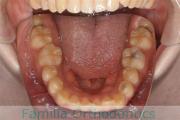

下の前歯が後ろにあるのが気になるとのことで来院されました。非抜歯で行うことも可能でしたが、上下左右から小臼歯抜歯をして治療を行うことをご希望になりました。

マルチブラケット法にて治療を行い、約3年、40回の通院が要でした。

かみ合わせが深い(上の前歯で下の前歯が覆われてしまう)ので、保定をしっかりしないと、また深くなってきてしまいやすいです。

上顎

下顎